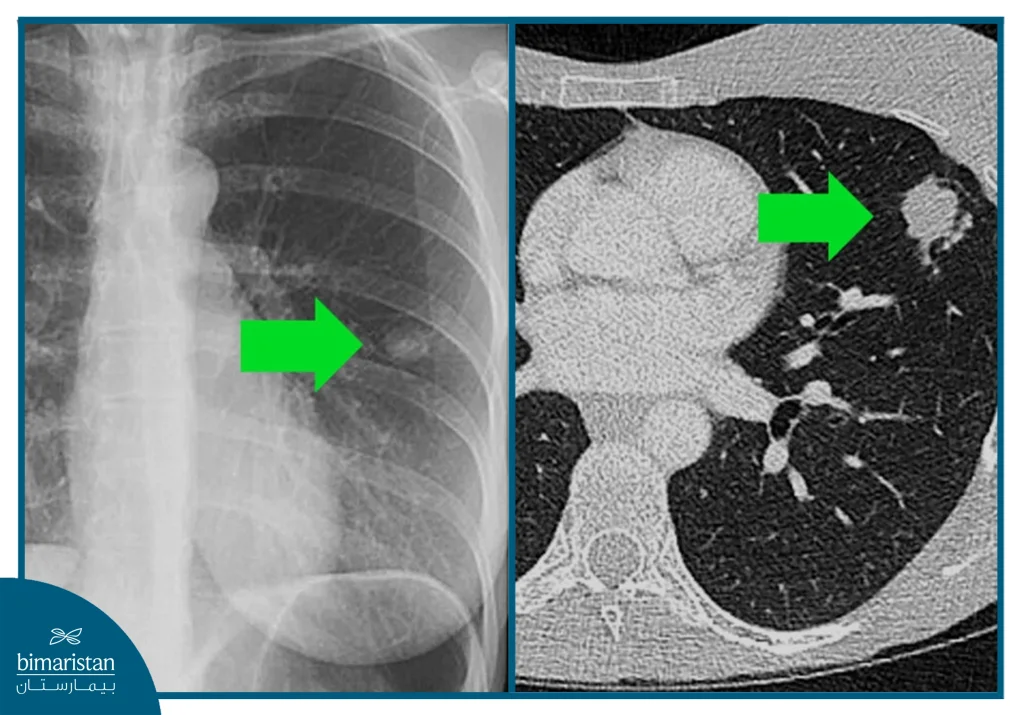

Radiological examinations play a pivotal role in tuberculosis diagnosis, as they help assess the extent to which the lungs or other organs are affected and determine the stage of infection, and although the laboratory test is the final confirmation of the diagnosis, imaging is an important tool to guide the doctor and follow the progression of the condition. The most important tests include

- Chest X-ray: Used as an initial test to evaluate the lungs, it may show cavities, fibrosis, or calcifications characteristic of tuberculosis infection, but it is not enough alone to confirm the diagnosis.

- CT scan: Shows more detail than an X-ray and helps detect small lesions or deep cavities, and is useful in assessing the extent of infection within the chest.